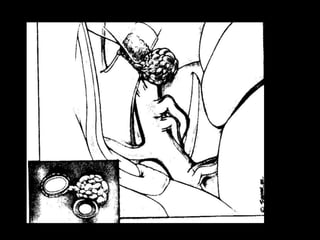

Surgery

• Simpson

• Kobayashi and associates-microscopic

• Location decides extent of resection and thus

recurrence

• Yamasaki&colleagues-3 yr followup(VEGF&MIB-1)

• Extent of removal*